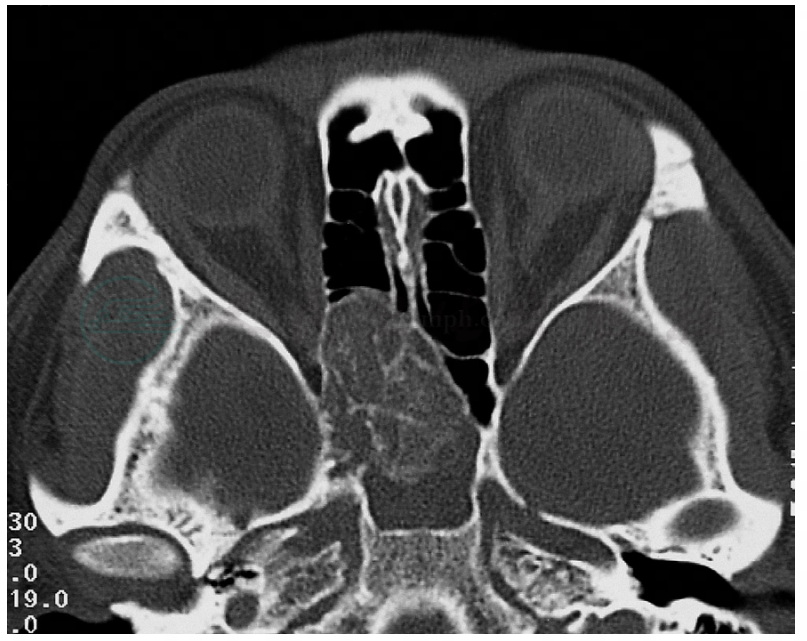

肿瘤可发生于鼻腔和(或)鼻窦,以筛窦多见,肿瘤发生于单侧较多,增大后可累及双侧。CT直接征象为鼻腔或筛窦内软组织密度肿块,肿块较小时呈乳头状,密度均匀,增强后轻度强化。本病可引起骨质吸收破坏或骨质增生,如发生恶变,骨质破坏更加明显(图1~3)。复发者多显示为鼻腔鼻窦术后改变。肿瘤阻塞鼻窦开口时引起继发性鼻窦炎改变,CT平扫一般不容易区别肿瘤与继发炎性改变,此时可行增强扫描,实性肿块部分有强化改变。肿瘤增大后可侵入眼眶或前颅窝。肿瘤迅速增大,骨质破坏明显时,应考虑有无恶变可能。本病的MRI表现:多数病变信号均匀,T1WI和T2WI表现为低到中等信号,中度强化,在增强的T1WI表现为条索样或脑回样改变(图4)。MRI易区分肿瘤与伴发的阻塞性炎症,阻塞性炎症多为潴留黏着分泌物,在增强T1WI和T2WI上,表现为信号减弱(图5)。

图1鼻腔、鼻窦内翻性乳头状瘤(右侧)

轴位CT显示上颌窦内壁骨质压迫部分吸收